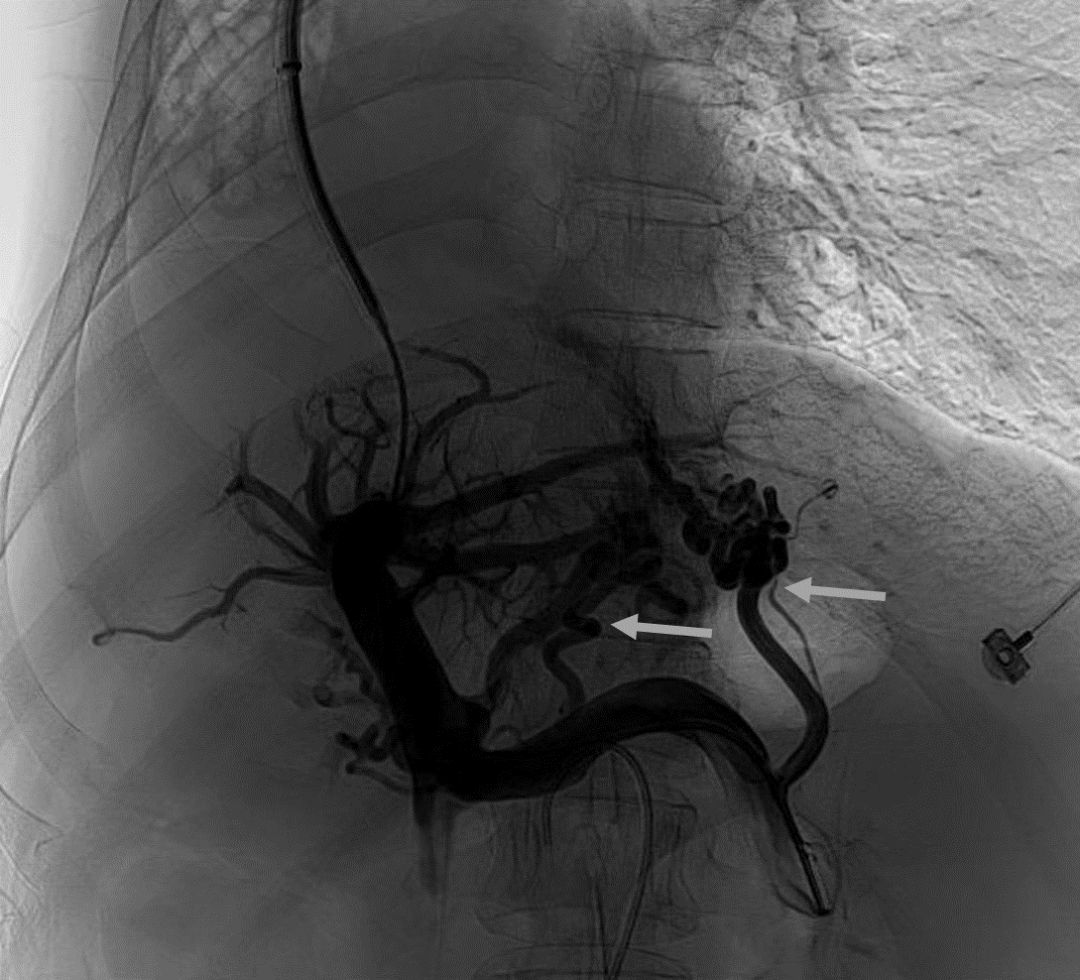

韓國宏教授介紹,TIPS手術(shù)是通過在肝靜脈與門靜脈之間的肝實(shí)質(zhì)內(nèi)建立分流通道,通過降低門靜脈壓力來預(yù)防和治療因門靜脈高壓引起的食管胃底曲張靜脈破裂出血或頑固性腹水。該手術(shù)不用開刀、創(chuàng)傷小、操作過程復(fù)雜、技術(shù)難度大、安全風(fēng)險(xiǎn)高,是目前外周血管介入中難度最大的手術(shù)之一。再加上人群中右位心發(fā)病率極低(約萬分之一),經(jīng)查閱文獻(xiàn),在國內(nèi)外尚未有類似病例報(bào)道,無經(jīng)驗(yàn)參考。在右位心基礎(chǔ)上行TIPS術(shù),無疑是難上加難。我們反復(fù)研究患者肝臟及心血管的特殊情況,詳細(xì)討論了手術(shù)方案,決定放棄常規(guī)的肝靜脈穿刺,另辟蹊徑,選擇高難度高風(fēng)險(xiǎn)的肝后段下腔靜脈穿刺門靜脈左支,憑借多年的經(jīng)驗(yàn)和嫻熟的技術(shù)最終成功的在下腔靜脈與門靜脈之間放置了TIPS專用支架,術(shù)后門靜脈壓力梯度從術(shù)前的19mmHg降至3mmHg,曲張靜脈消失,解決了困擾曹女士多年上消化道出血的困擾。患者術(shù)后第二天即可正常下床活動(dòng)。